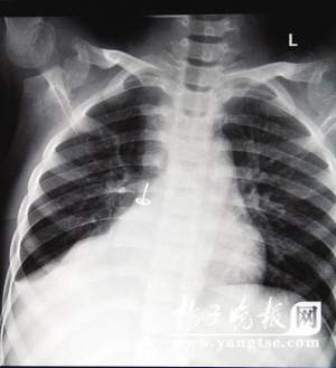

從片子上,圖釘在孩子右肺里“潛伏”得很深,卡在右下葉支氣管。南京市兒童醫院耳鼻喉科周艾醫生表示,由于圖釘堵住了孩子支氣管的通道,導致右肺葉不擴張,肺部已經發生了實質性的改變,用擴張來進行氧氣交換的肺泡都已經“癟”下去了,所以孩子的肺部功能非常弱。從片子上看,孩子的右肺已經嚴重“萎縮”,比左肺小了一大圈。